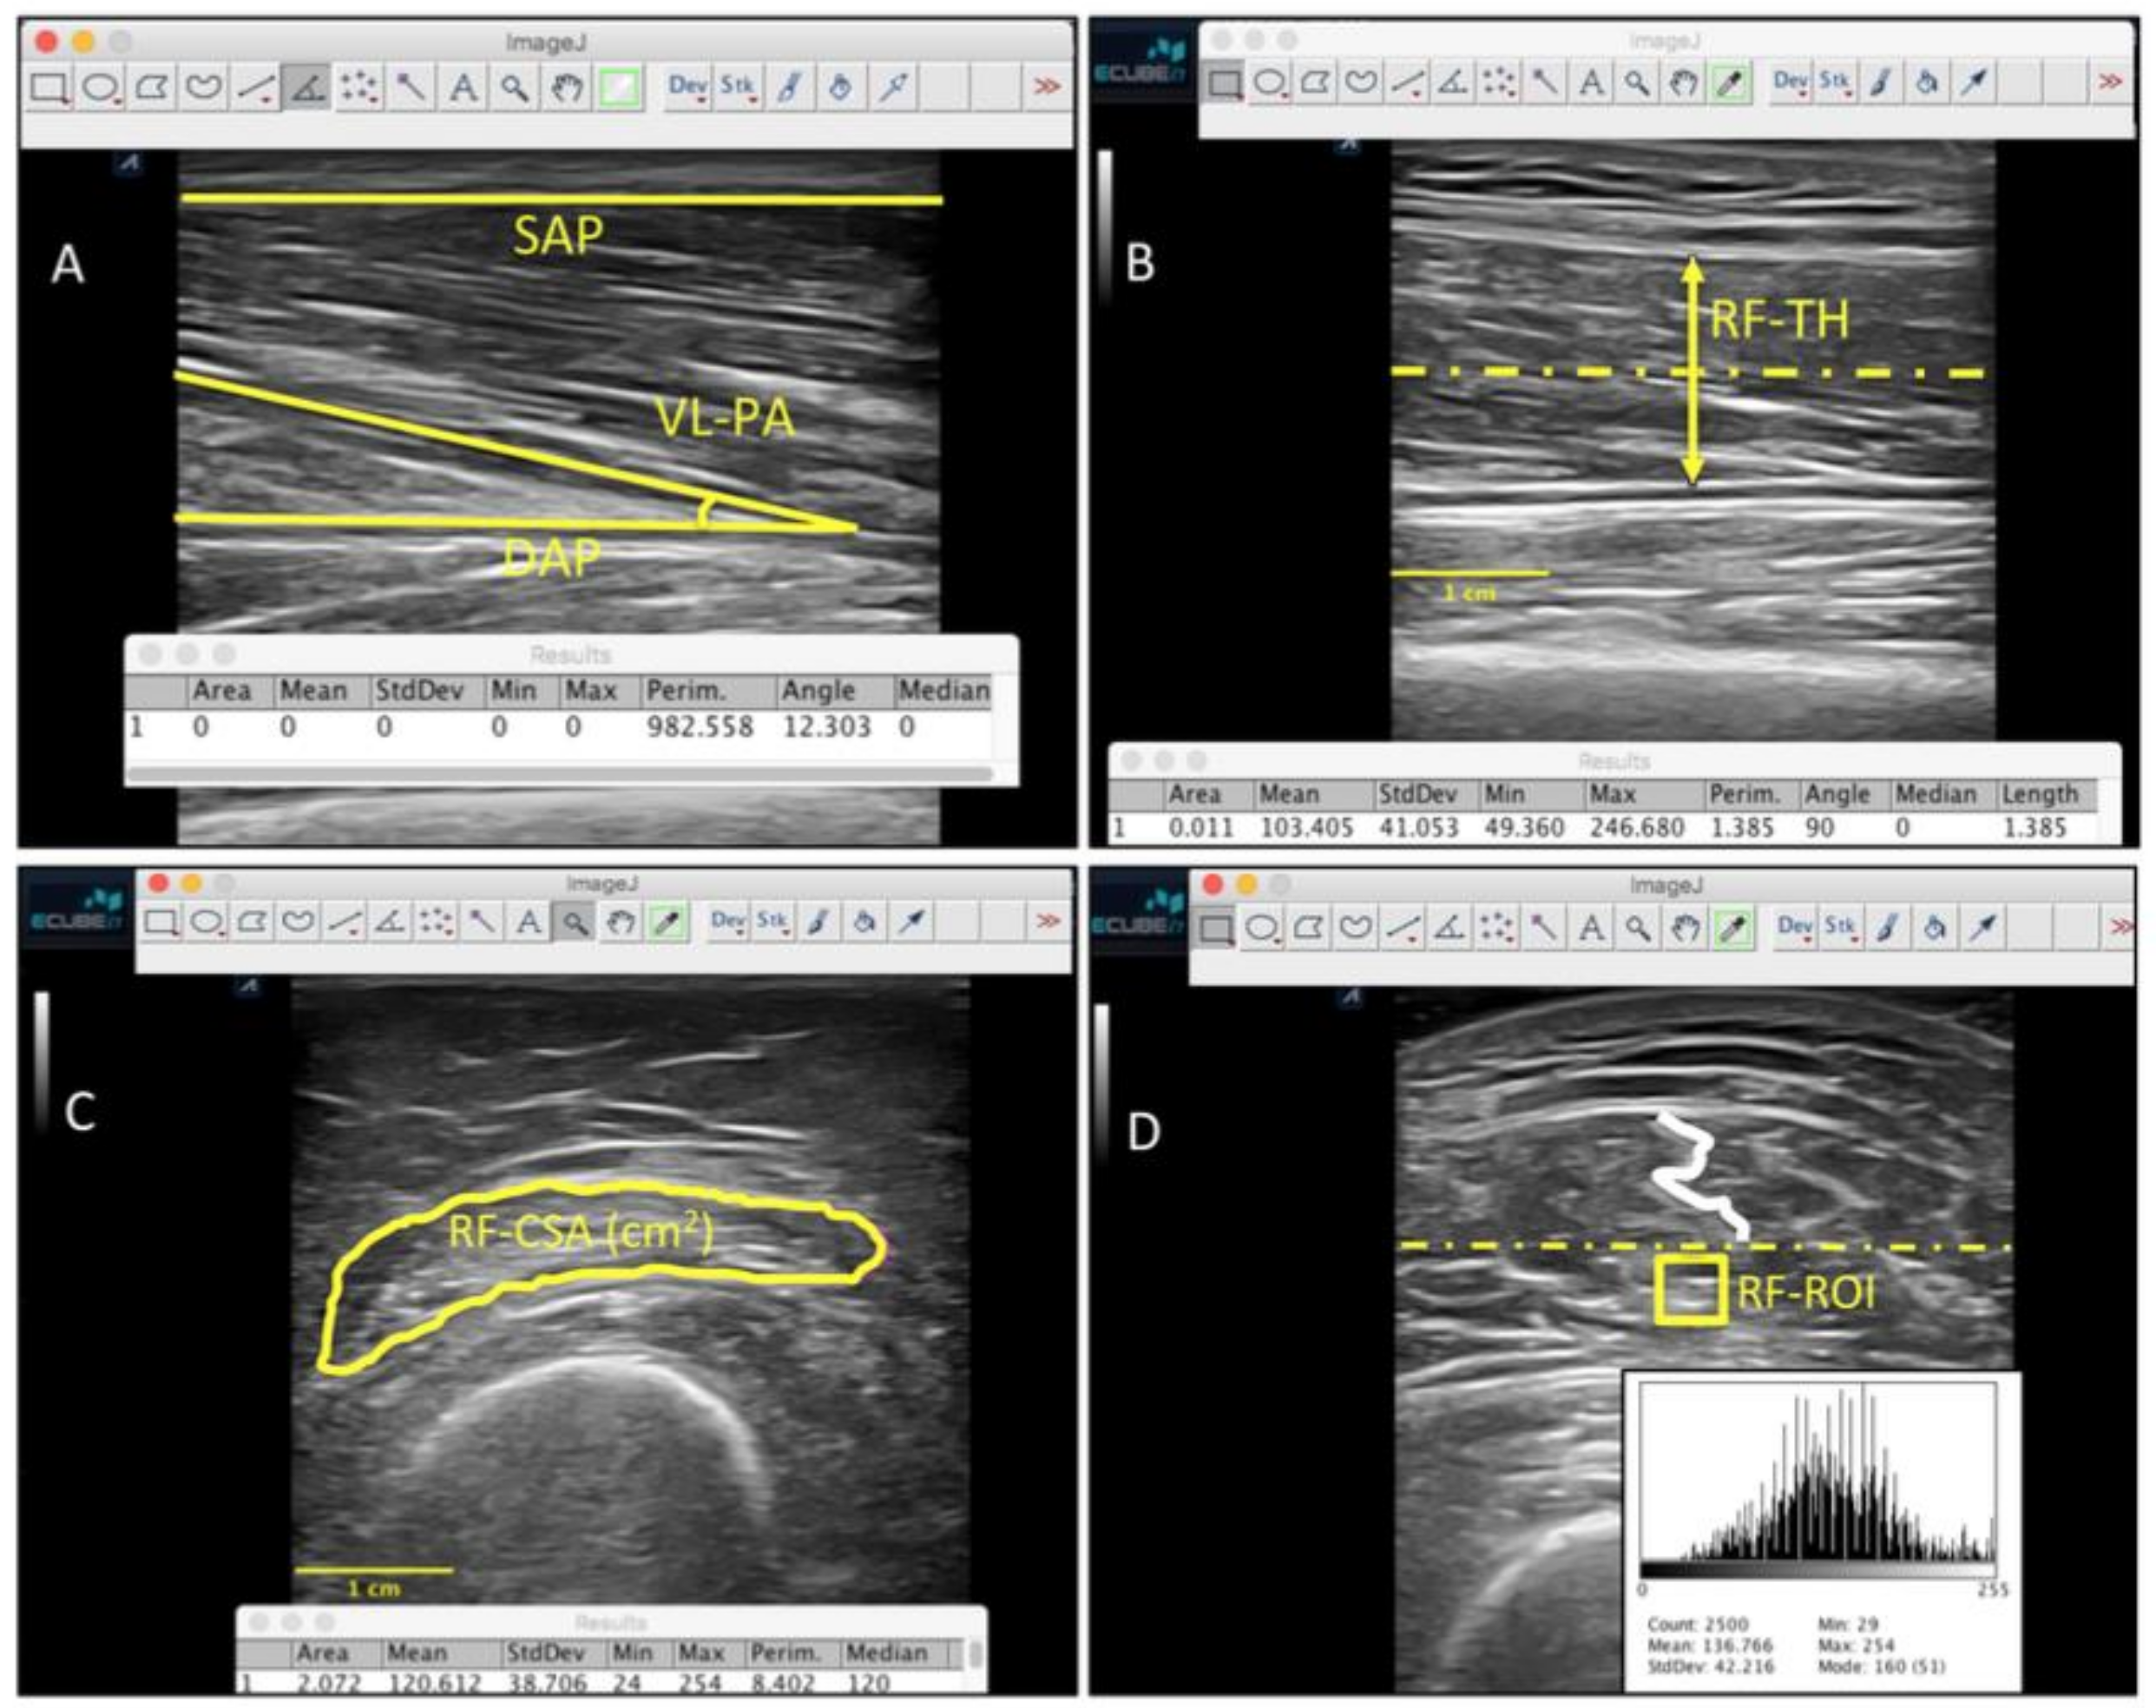

2.9. Ultrasound Imaging Evaluation

2.10. Functional Parameters Assessment